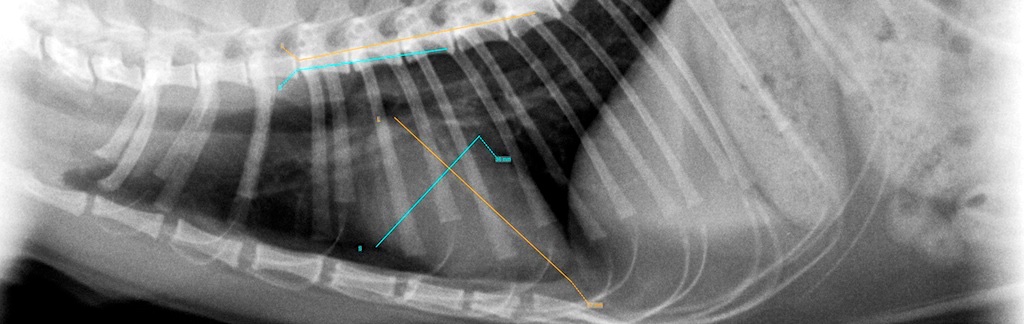

In unserer Praxis kommt ein digitaler Röntgenscanner zum Einsatz. Damit erreichen wir eine deutliche Qualitätssteigerung in der Diagnostik, aber auch Archivierung und Verwaltung unserer Röntgenbilder. Die Strahlenbelastung unserer Patienten ist ebenso verringert, wie die Umweltbelastung durch die sonst notwendigen Entwicklerchemikalien.

Durch die Möglichkeiten digitaler Bildbearbeitung und diverser Software können wir genaue Messungen durchführen. z.B.: exakte HD-Messung, oder objektive Herzgrößenmessungen.

Wegen der Qualität unserer Bilder und dem hohen Maß an Unbefangenheit in der Befundung, sind wir seit dem Jahr 2000 Vertrauenstierarzt-praxis, sowie offizielle HD, ED/OCD - Röntgenstelle des SVÖ und ÖKV.